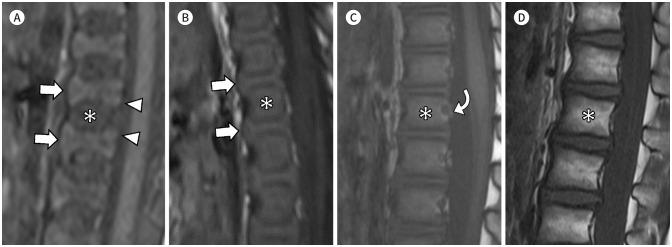

MRI plays a crucial role in bone marrow (BM) assessment, and has very high sensitivity in diagnosing marrow disorders. However, for radiologists who may not frequently encounter pediatric imaging, distinguishing pathologic BM lesion from normal BM can be challenging. Conditions involving the BM in pediatric patients, such as leukemia and metastatic neuroblastoma, often manifest with diverse musculoskeletal symptoms and may be diagnosed using musculoskeletal MRI examinations. Accurate interpretation of pediatric MRI requires not only an understanding of the normal composition of BM but also an awareness of agerelated developmental changes in the marrow and familiarity with conditions that commonly involve pediatric BM. We aim to describe the composition of normal BM and outline the normal and abnormal MRI findings in pediatric BM. Additionally, we aim to present clinical cases of malignant BM disorders including leukemia, neuroblastoma metastasis, and other malignant BM disorders.

磁共振成像(MRI)在骨髓(BM)评估中起着至关重要的作用,并且在诊断骨髓疾病方面具有很高的敏感性。然而,对于可能不经常接触儿科影像的放射科医生来说,区分病理性骨髓病变与正常骨髓可能具有挑战性。儿科患者中涉及骨髓的疾病,如白血病和转移性神经母细胞瘤,通常表现为多样的肌肉骨骼症状,可通过肌肉骨骼MRI检查进行诊断。准确解读儿科MRI不仅需要了解骨髓的正常组成,还需要认识到骨髓中与年龄相关的发育变化,并熟悉常见累及儿科骨髓的疾病。我们旨在描述正常骨髓的组成,并概述儿科骨髓的正常和异常MRI表现。此外,我们旨在展示包括白血病、神经母细胞瘤转移和其他恶性骨髓疾病在内的恶性骨髓疾病的临床病例。